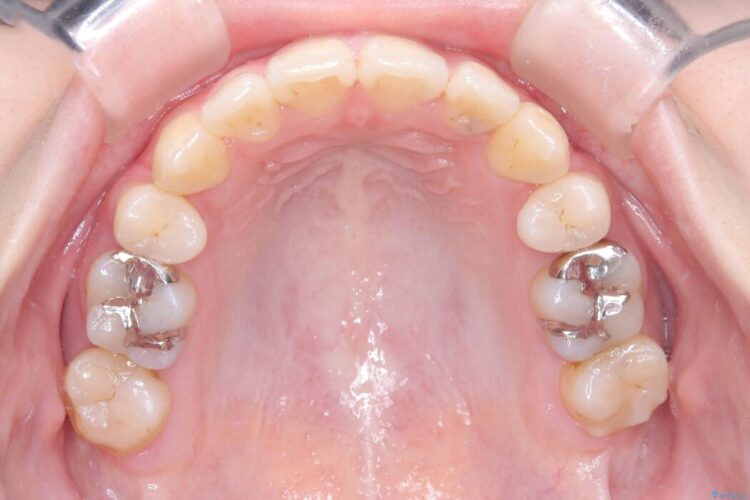

- 矯正装置:ワイヤー矯正(クリア装置)

開咬、叢生、八重歯が気になるとご来院された患者様です。

精密検査の結果、上顎左右4番および下顎左右5番の計4本を抜歯し、目立ちにくいクリア装置にて治療を行いました。

気になっていたガタつきや開咬が改善され、見た目だけでなく咬み合わせの機能面も大きく向上し、大変ご満足いただけました。